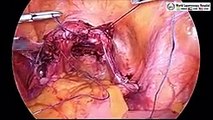

Suturing and knotting in laparoscopy involves precise techniques due to limited space. Surgeons use specialized instruments to create secure and accurate sutures. Laparoscopic knot tying requires skill to manage the challenges of working within a confined environment. The proficiency in suturing and knotting in laparoscopy is crucial for successful minimally invasive surgeries, ensuring effective wound closure and minimizing postoperative complications. Read more- https://www.laparoscopyhospital.com/SERV01.HTM